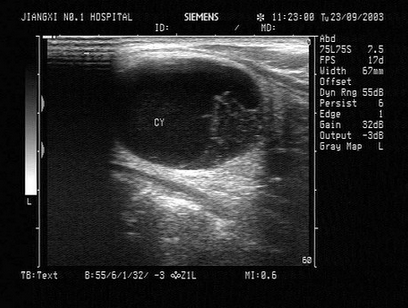

52、单项选择题

女性,29岁,停经28周,产前超声检查如图,最可能的诊断为()

A.胎儿畸形,脑积水

B.胎儿畸形,腹壁裂

C.胎儿畸形,室间隔缺损

D.胎儿畸形,无脑儿

E.胎儿畸形,露脑畸形